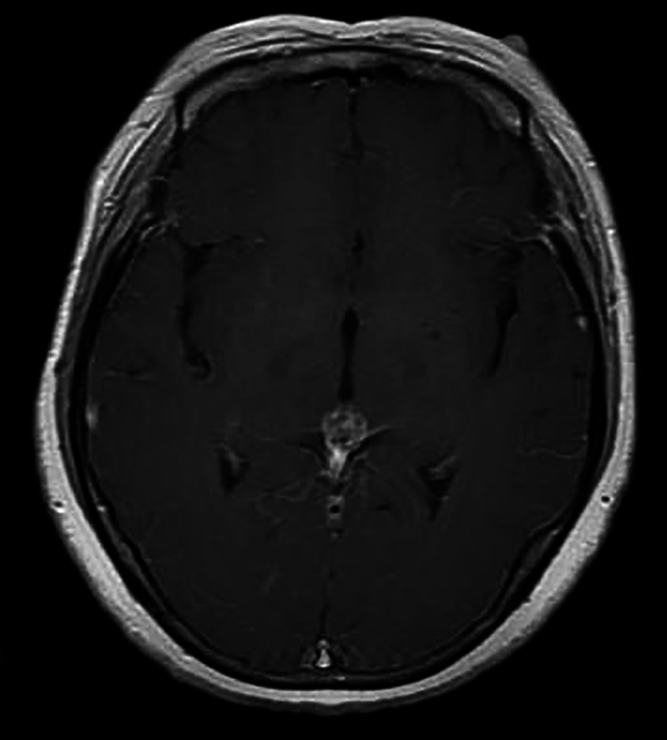

Background: Primary pineal melanoma is a rare tumor characterized by a high propensity for progression and recurrence. The imaging complexity of the melanoma will pose significant challenges for preoperative diagnosis. Definitive diagnosis necessitates histopathological examination.

Observations: The authors present the case of a 49-year-old woman presenting with headache accompanied by nausea and vomiting. Imaging revealed a pineal tumor with subarachnoid hemorrhage. She underwent her first craniotomy at another hospital. Four months after surgery, she was sent to the authors' hospital for a second craniotomy due to recurrent cerebral hemorrhage. The postoperative pathological diagnosis was malignant melanoma in the pineal region.